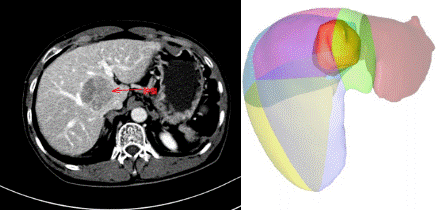

勇闯“禁区”!——泸州市中医院再攀技术高峰,成功开展“剥蛋黄”手术经肝脏正中裂将肝脏劈开,在布满粗大血管的肝脏背侧,将肿瘤从被血管包绕的肝脏尾状叶切除,并最大限度保留正常肝组织。该手术犹如“火中取栗”,要求手术医生必须有“庖丁解牛”般的精准,因此,该手术方式被东方肝胆医院的周伟平...